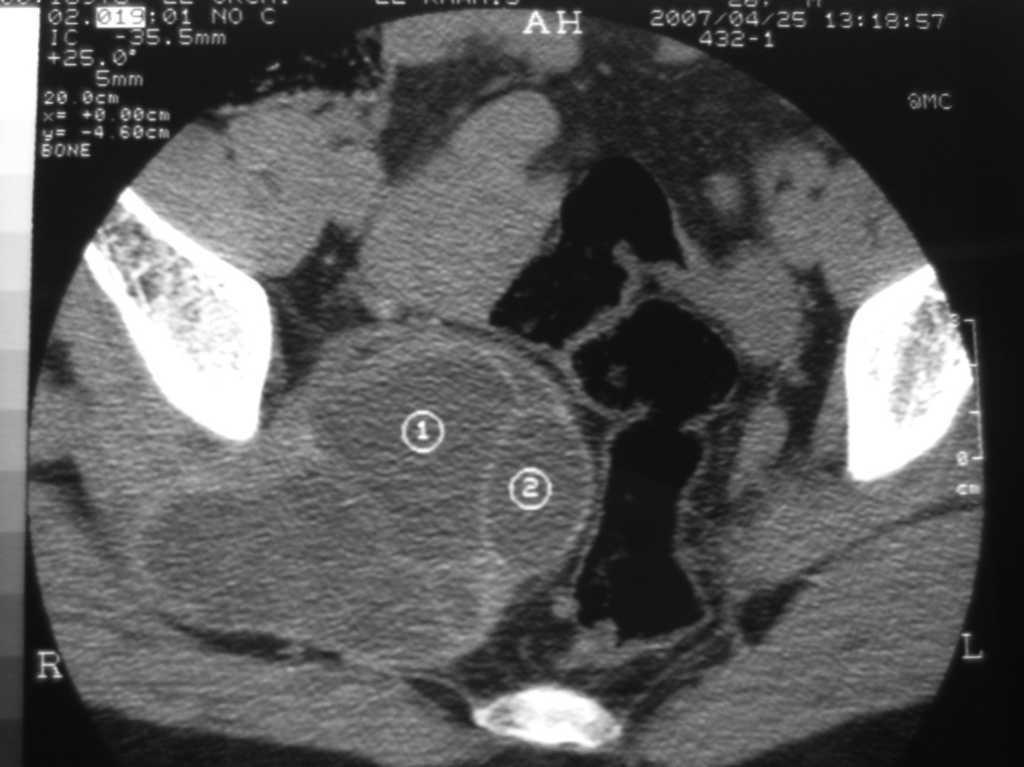

Fig. 2 – Masa bilobulada, multiseptada a nivel del presacro derecho en la tomografía computarizada abdominopelviana.

Presentamos el caso de un paciente de 26 años de origen marroquí, que acude a urgencias por cuadro de dificultad para la marcha, dolor lumbar irradiado a la pierna derecha con pérdida de fuerza y atrofia muscular, de 6 meses de evolución. A la exploración presenta marcha en estepaje, pie varo, importante atrofia muscular en la región gemelar y peronea derecha, parálisis de la flexión dorsal e hipoalgesia del cuarto y el quinto dedo del pie derecho. El abdomen es blando y depresible, sin masas ni megalias. Al tacto rectal se palpa tumoración en la cara lateral derecha del recto que respeta la mucosa. Se realiza examen neurofisiológico que indica el origen proximal alto intrapelviano del cuadro de axonotmesis ciática que presenta el paciente. En la resonancia magnética (RM) de la columna lumbar se identifica una lesión quística compleja intramuscular (piriforme derecho) de 11 ×6 cm de diámetro, con compresión extrínseca del plexo sacro derecho (fig. 1). Se realiza tomografía computarizada (TC) abdominopelviana que informa de masa quística bilobulada, multiseptada bien diferenciada a nivel del presacro derecho, que se extiende por escotadura ciática hasta la región glútea (fig. 2). Se consideran entre los diagnósticos diferenciales el origen infeccioso de la lesión (hidatidosis, cisticercosis) o tumoral (mixoma intramuscular, schwannoma). La serología para hidatidosis resulta positiva (1/320), por lo que se inicia tratamiento preoperatorio con albendazol. Se interviene al paciente mediante abordaje anterior, y se aprecia una tumoración quística posterior al plexo sacro, que comprime y desplaza anteriormente el nervio ciático. Se realiza exéresis completa del quiste hidatídico, previa protección del campo quirúrgico con suero salino hipertónico al 20%. No se identifican quistes en otras localizaciones. Durante el postoperatorio el paciente evoluciona favorablemente, y recibe el alta hospitalaria el 16.° día postoperatorio. En la revisión a los 6 meses el paciente se encuentra sin dolor, y va recuperando masa muscular y funcionalidad de la pierna derecha.